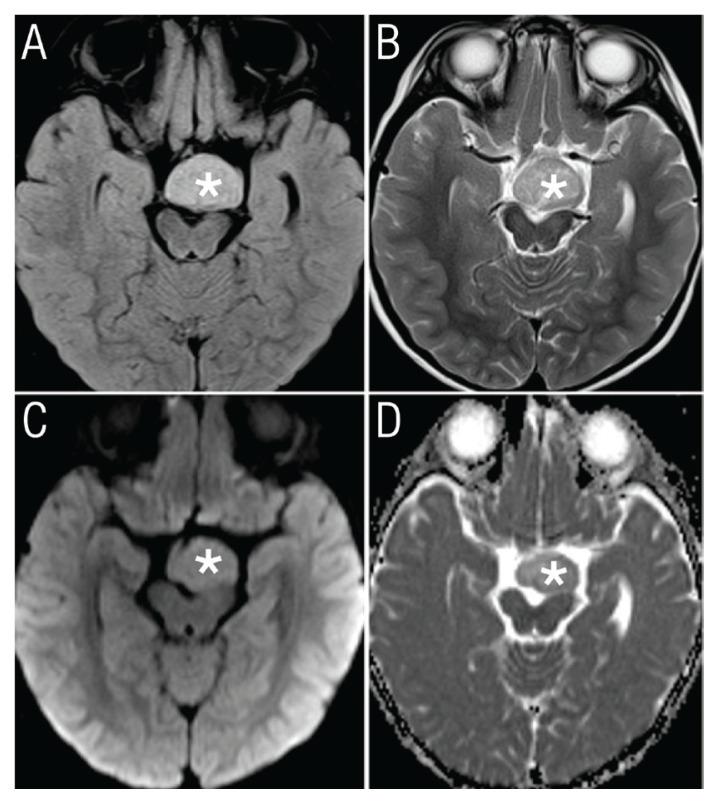

Inappropriate Laughter in a Patient with Hypothalamic Hamartoma.

Sultan Qaboos Univ Med J. 2020 May;20(2):e231-e233. doi: 10.18295/squmj.2020.20.02.016. Epub 2020 Jun 28.